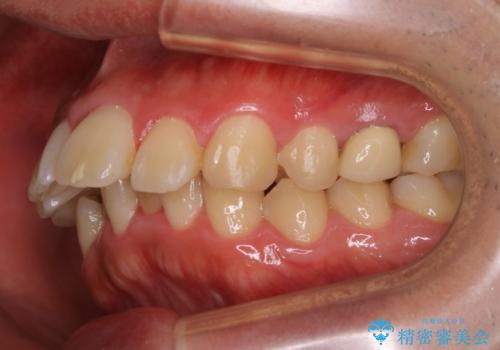

- 3年

- 30回以上

- 90万円費用は治療当時の料金となります